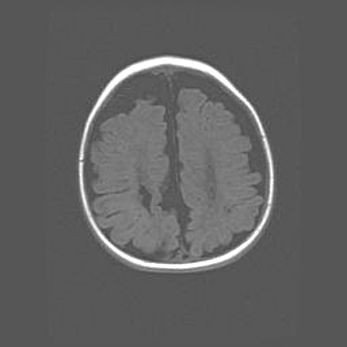

Открытая гидроцефалия.

Возраст: 6 месяцев 15 дней

Вес: 6200 г

Пол: женский

Окружность головы: 41 см

Срок гестации: 38 недель

Гидроцефалия головного мозга у новорожденных – это скопление избыточного количества цереброспинальной жидкости в головном мозге. Ее избыточное скопление в мозге приводит к патологическому расширению желудочков мозга (четырех полостей, расположенных в глубине белого вещества мозга, заполненных цереброспинальной жидкостью и связанных узкими проходами).

Открытый тип гидроцефалии (сообщающаяся) наблюдается тогда, когда нарушен механизм всасывания ликвора в системный кровоток. При этом типе причиной заболевания чаще всего является перенесенные ранее инфекции (например: менингит),  либо же наличие крови в субарахноидальном пространстве.